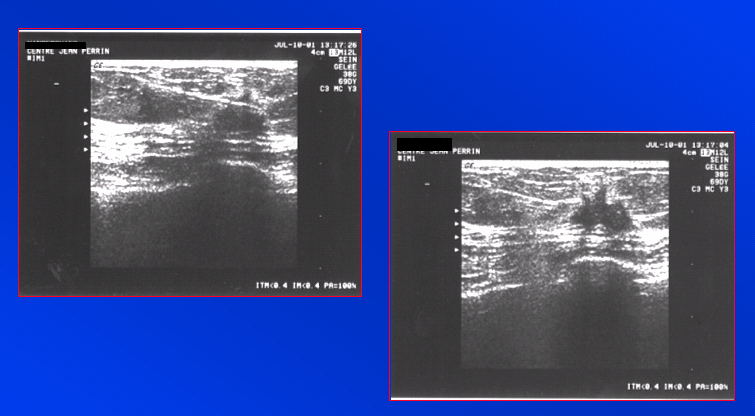

Micro-biopsie pré-thérapeutique d’une lésion ACR 5 | Iconographie précédente | Retour cours | Index iconographique | Iconographie suivante |